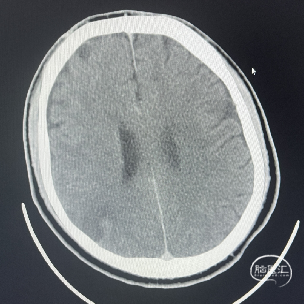

辅助检查:CT见右侧基底节区及右顶叶低密度病灶。

术后CT:术后即刻CT,以及术后24h CT。